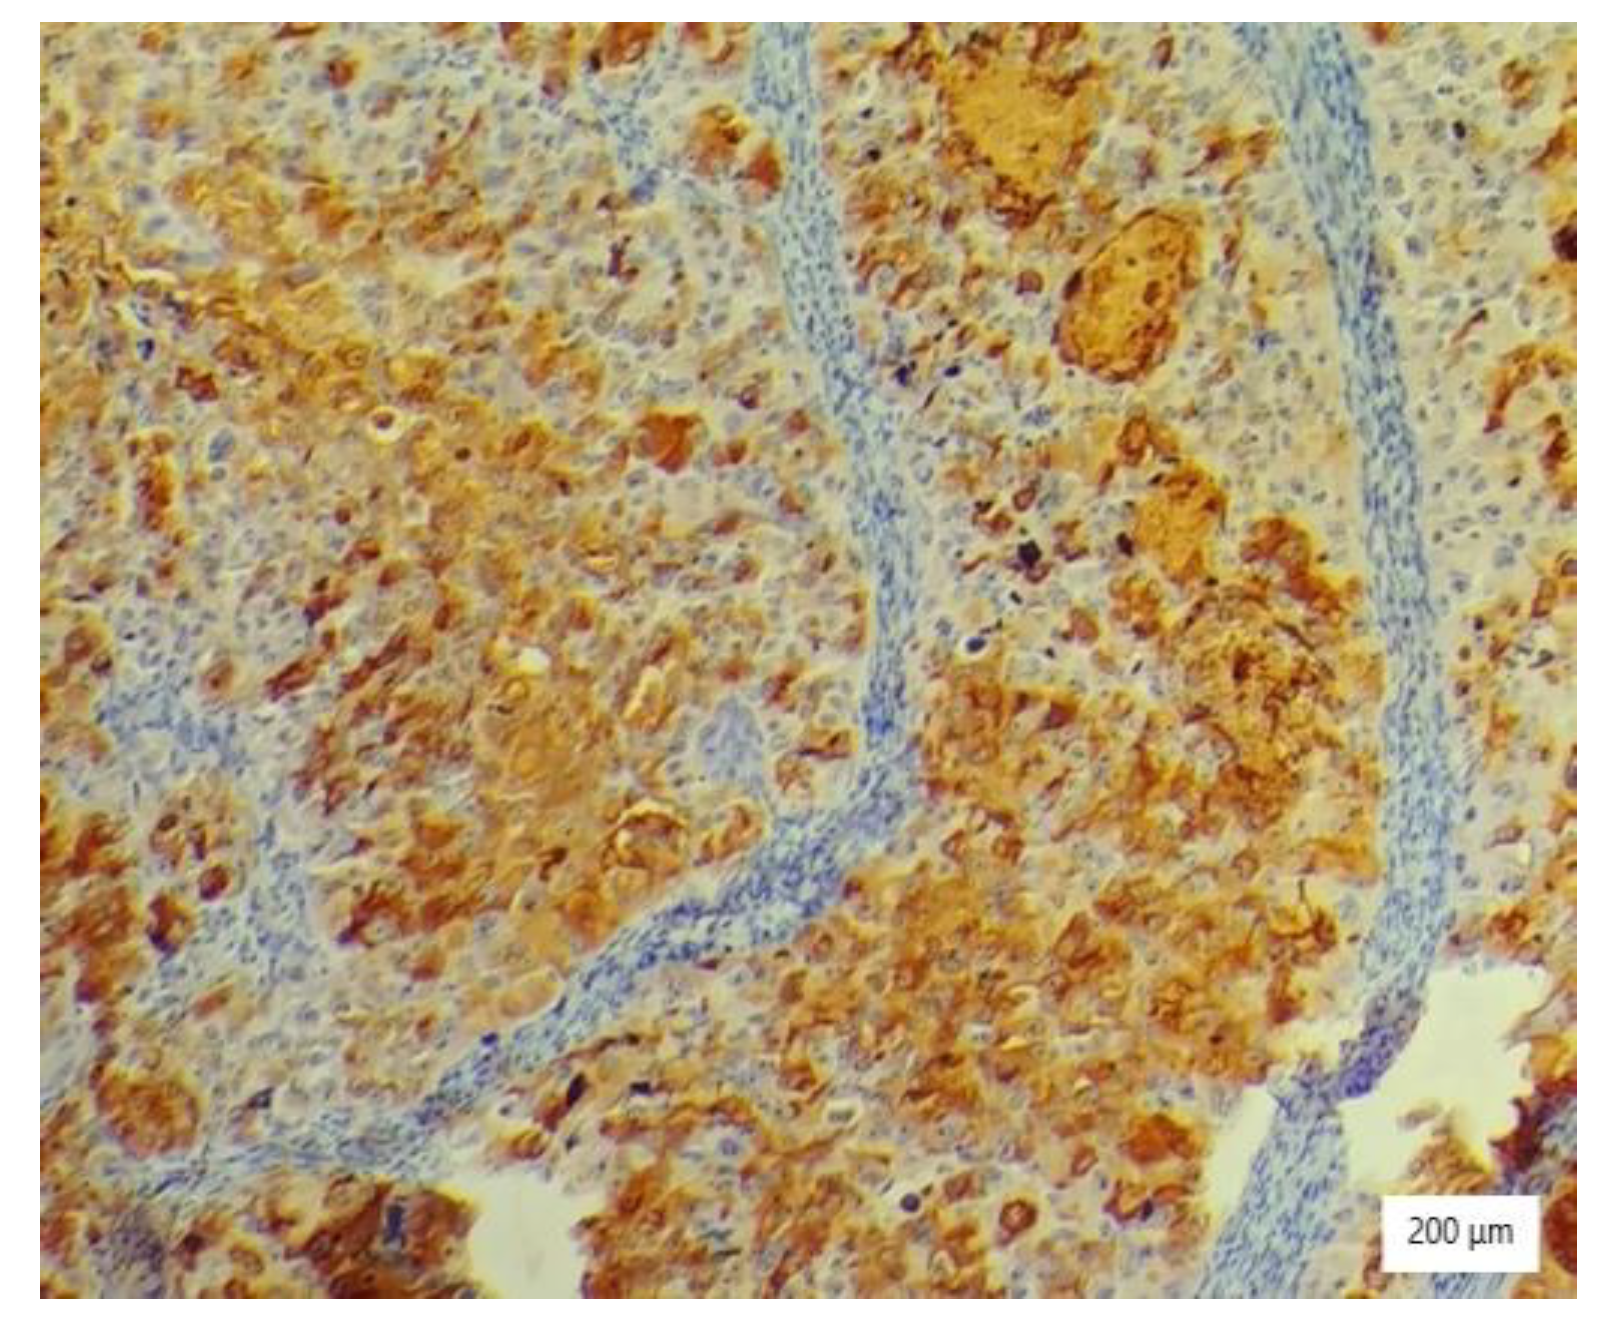

2.4. Histopathology Findings

The microscopic analysis of the cervical mass biopsy showed the presence of the following morphological aspects: mixed architecture with solid and tubulocystic patterned areas; mainly composed of nests of cells with clear or eosinophilic cytoplasm (intracytoplasmic glycogen); and prominent hyperchromatic nuclei, some with round nucleoli and high mitotic activity (16/10 HPF) (Figure 2, Figure 3 and Figure 4). Additionally, we noted abundant inflammatory infiltrate that was mainly made up of the lymphocytes and plasmacytes present in the hyalinized stroma, and this was determined to be associated with the area of necrosis. Periodic acid–Schiff staining was strongly positive in the cytoplasm, consistent with glycogen (Figure 5). Immunohistochemical staining showed a diffuse positive reaction for CK AE1/AE3, PAX8, and AMACR; rare cells showed CEA-positive expression; and there was a negative reaction for p63, CD30, OCT4, ER, SALL4, synaptophysin, CD56, and p16, which were focally positive in tumor cells (Figure 6, Figure 7, Figure 8, Figure 9, Figure 10 and Figure 11). The histological diagnosis was HPV-negative clear cell adenocarcinoma of the uterine cervix.

Figure 6. Diffuse AE1/AE3 immunostaining of large neoplastic cells with clear cytoplasm (×200).